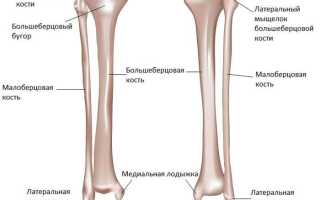

Где расположена большая берцовая кость? Она находится ниже колена и является частью скелета свободной нижней конечности, то есть голени. В этой области также располагается малая берцовая кость. Большеберцовая кость находится ближе к внутренней стороне голени, в то время как малоберцовая расположена снаружи. Из этих двух костей именно большеберцовая, соединяясь сверху с бедренной, участвует в формировании коленного сустава.

В нижней части малоберцовая и большеберцовая кости соединяются со стопой, образуя внешнюю и внутреннюю лодыжку соответственно. Это соединение называется голеностопным суставом. Он состоит из тонких связок и сухожилий и обильно снабжен кровеносными сосудами и нервами. Голеностопный сустав испытывает значительные нагрузки от веса тела и подвержен вывихам и переломам. Травмы в этой области часто сопровождаются сильной болью, а процесс восстановления может занять много времени.

Состоит из центральной части и двух концов: ближнего и дальнего. Ближняя к бедру (верхняя) зона имеет два мыщелка: один расположен с внутренней стороны ноги, а другой – с внешней. Между ними находятся две суставные поверхности, которые соединяются с головкой бедра. Эти поверхности разделены межмыщелковым возвышением, значение которого трудно переоценить, так как именно к нему прикрепляются все внутренние связки коленного сустава, без которых движение было бы невозможно.

На передней поверхности большеберцовой кости имеется шероховатая выпуклая область, к которой прикрепляется сухожилие четырехглавой мышцы бедра. Нижняя часть кости имеет утолщение – медиальную лодыжку, на которой расположены поверхности для соединения с таранной костью стопы и малоберцовой.

Малоберцовая

Малоберцовая кость имеет два конца: ближний и дальний, а также тело. Ближний конец представляет собой головку малой берцовой кости, на которой расположены соответствующие участки для соединения с большой берцовой костью, включая шероховатости и суставные поверхности. Кроме того, на головке находится верхушка (апекс). Нижняя часть малоберцовой кости формирует боковую лодыжку, которая соединяется со стопой.